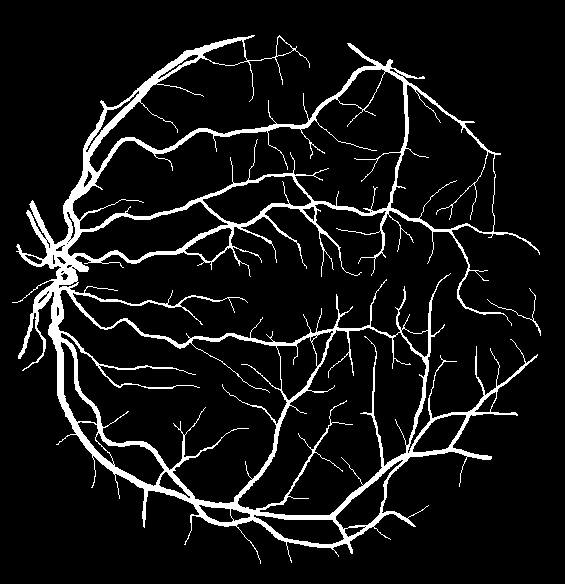

The visual differentiation between arteries and veins can be difficult in some cases, like small vessels with poor contrast and not clearly connected to a specific arterial or venular tree. These cases can be identified with certainty as vessels, but their classification into arteries and veins is uncertain, even for an expert. Additionally, it is common to find crossings between arteries and veins in the retina. Thus, although for these positions either the artery or the vein is above the other, these pixels can be regarded as simultaneously belonging to both types of vessels. This allows to account for continuous arterial and venular trees regardless of crossings below the other one. The identification of these two special situations (uncertain vessels, and vessel crossings) is common in manually annotated retinal vessel classification datasets [38, 42, 43, 44]. Figure 1 shows an example of a ground truth image from the RITE dataset labelled this way, along with its decomposition into arteries, veins, crossings and uncertain vessels.

Also, an example of a retinography and its corresponding vasculature segmentation and A/V classification ground truths is depicted in Figure 6.

In order to train the networks following the traditional and MS approaches, the ground truth images from the RITE dataset are adapted, in each case, to the output of the network. In the traditional approach, each pixel of the ground truth is assigned to either background, artery, vein or “uncertain or crossing” class, which comprises both uncertain vessels and crossings. The resulting ground truth is a grayscale image in which each pixel has a numeric label of the class to which it belongs. On the other hand, in the MS approach, each pixel is assigned to any number of the following classes: artery, vein and vessel. In this case, crossings belong to the three classes, and uncertain vessels belong only to the “vessel” class. Background pixels are not assigned to any class. The resulting ground truth is an RGB image in which each channel contains a manual segmentation mask of one of the aforementioned structures. An example of a RITE ground truth adapted to both the traditional and the MS approaches can be found in Figure 7.